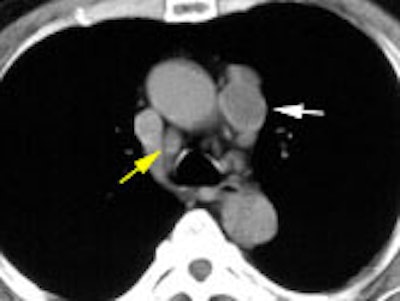

Example: This patient with a left lung non-small cell lung cancer demonstrated a pathologic aorto-pulmonary window node (N2) by CT size criteria (white arrow), and a non-pathologic retrocaval-pretracheal contralateral mediastinal node (N3) (yellow arrow). PET-FDG images revealed increased tracer accumulation within both nodes, consistent with metastases. (Case courtesy of H. Page McAdams MD, Department of Radiology, Duke University Medical Center)